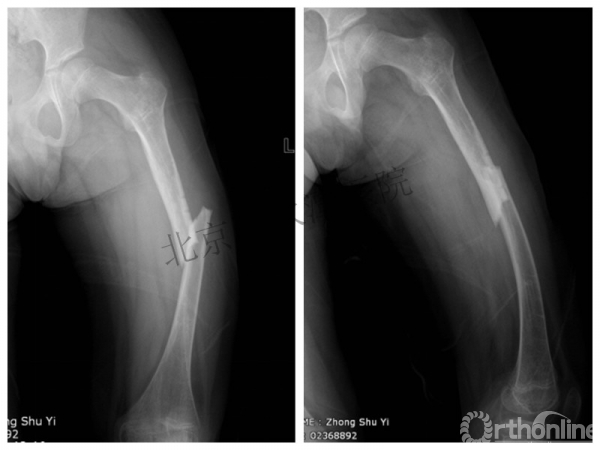

又过了4年!时间来到2015年

一年以后顺利愈合,实则危机四伏

数月后再骨折!牵引!